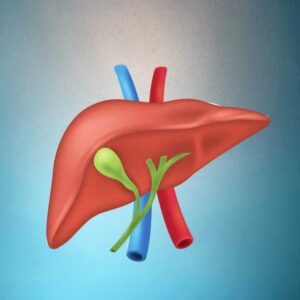

Liver function tests are advised by doctors to find out if the liver is functioning properly or if there is any problem with the liver. main liver function test bill Rubin Alkaline phosphate, AST/SGOT, ALT/SGPT, GGT, L proteins, albumin, globulin, and albumin/globulin can be detected through a liver function test.

Red blood cells in the body live for about 120 days and then die. when red blood cells die. Bilirubin is released. We call this indirect bilirubin. This indirect bilirubin goes to the liver and gets converted into direct bilirubin. If there is a liver problem, this bilirubin will increase; mainly the direct bilirubin will increase.

When any stones form in the liver, alkaline phosphate increases, which is a product of the liver itself. Alkaline phosphate increases during pregnancy. Bones release alkaline phosphate, which is why children have high levels of alkaline phosphate.

is elevated when there is any problem with the liver. AST is also produced by the liver, kidneys, and heart muscles.

Gamma-glutamate transaminase: if it is high, it can cause liver problems in people who drink alcohol.

The liver makes proteins for us. Who has liver problems? Total protein decreases, albumin decreases, and the AG ratio also decreases.